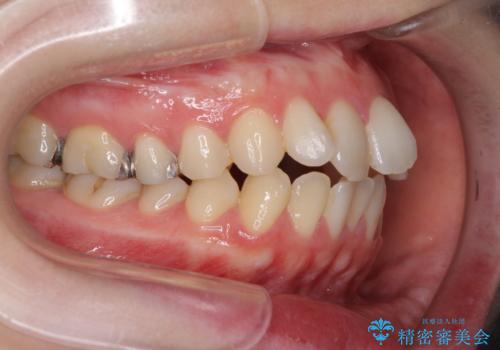

- 前歯のデコボコを気にして来院された患者様です。

下顎が骨格的にずれており、上下正中を合わせることは難しいことが予想されたため、デコボコの解消を主目的として、ワイヤー矯正を行うこととしました。